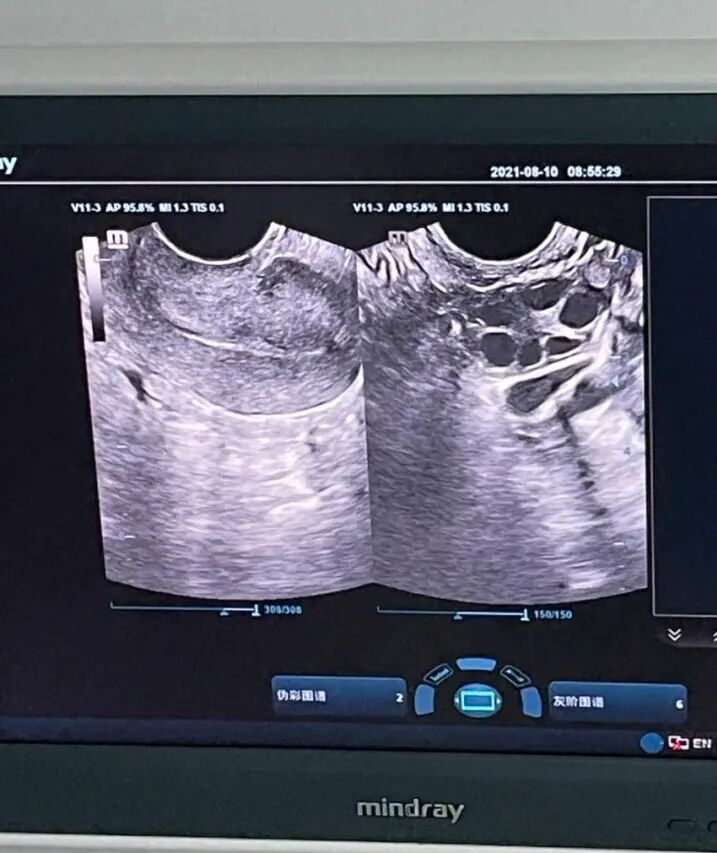

他们总结的第一个避坑要点:别信 “快速成功”“低价打包” 的噱头!正规试管周期至少 2-3 个月,费用明细会明确拆分医疗、助孕等项目。核查资质、拆分费用,这两步是跨境试管的 “安全门”。PART.02三阶段流程拆解,每个环节都有 “科学指南”2024 年初,夫妇俩与爱心麻麻一同开启试管周期,全程三个阶段环环相扣,每一步都藏着 “事半功倍” 的技巧。促排取卵阶段医生为太太定制低刺激方案:月经第 2 天开始用药,每周 2 次 B 超监测。“遵医嘱不擅自加药” 是关键—— 曾有患者自行加药导致卵巢过度刺激,而他们严格按剂量用药,10 分钟无痛取卵 12 枚,同步取精后筛选出 8 枚优质受精卵。